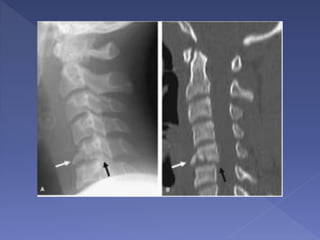

• Extensive

degenerative changes

noted but no gross

evidence of

malalignment

• The ALL, LF and

PLL are disrupted.

• There is widening

of the interspinous

distance

• Edema in the

posterior paraspinal

soft tissues

• damaged

intervertebral disc

Discontinuity of the ligamentum flavum and

edema in the posterior paraspinal

musculature